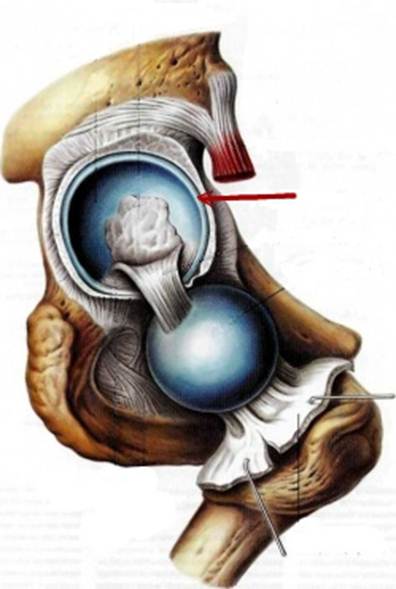

S: На рисунке обозначен art. Coxae (латинский язык).

S: Стрелка указывает на zona orbicularis

S: Стрелка указывает на lig. Ischiofemorale

S: Стрелки указывают на lig. iliofemorale

S: Стрелка указывает на lig. pubofemorale

S: Стрелка указывает на labrum acetabuli

S: Стрелка указывает на lig. Capitis femoris

S: Стрелка указывает на facies lunata